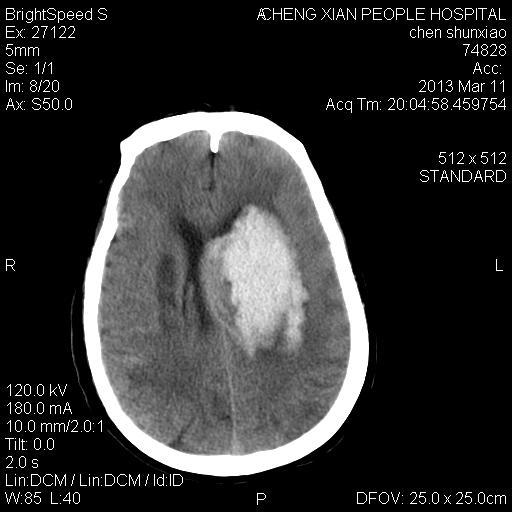

患者陈++,男,71岁。因“昏迷四小时,伴右侧肢体活动受限”以“脑出血”收住院。发病后12小时用“改良立体定向-软通道微创介入新技术治疗脑出血”。术后24小时颅内出血大部被清除,患者神志清晰。右侧肢体肌力0级。

患者陈++,男,71岁。因“昏迷四小时,伴右侧肢体活动受限”以“脑出血”收住院。发病后12小时用“改良立体定向-软通道微创介入新技术治疗脑出血”。术后24小时颅内出血大部被清除,患者神志清晰。右侧肢体肌力0级。